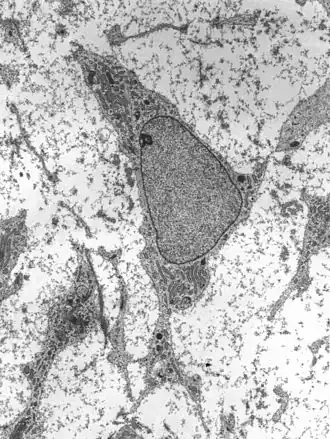

![]() Transmission electron micrograph of a mesenchymal stem cell displaying typical ultrastructural characteristics | |

Mesenchymal stem cells

Mesenchymal stem cells (MSC) or mesenchymal stromal cells, also known as medicinal signaling cells are known to be multipotent, which can be found in adult tissues, for example, in the muscle, liver, bone marrow and adipose tissue. Mesenchymal stem cells usually function as structural support in various organs as mentioned above, and control the movement of substances. MSC can differentiate into numerous cell categories as an illustration of adipocytes, osteocytes, and chondrocytes, derived by the mesodermal layer.[34] Where the mesoderm layer provides an increase to the body's skeletal elements, such as relating to the cartilage or bone. The term "meso" means middle, infusion originated from the Greek, signifying that mesenchymal cells are able to range and travel in early embryonic growth among the ectodermal and endodermal layers. This mechanism helps with space-filling thus, key for repairing wounds in adult organisms that have to do with mesenchymal cells in the dermis (skin), bone, or muscle.[35]

Mesenchymal stem cells are known to be essential for regenerative medicine. They are broadly studied in clinical trials. Since they are easily isolated and obtain high yield, high plasticity, which makes able to facilitate inflammation and encourage cell growth, cell differentiation, and restoring tissue derived from immunomodulation and immunosuppression. MSC comes from the bone marrow, which requires an aggressive procedure when it comes to isolating the quantity and quality of the isolated cell, and it varies by how old the donor. When comparing the rates of MSC in the bone marrow aspirates and bone marrow stroma, the aspirates tend to have lower rates of MSC than the stroma. MSC are known to be heterogeneous, and they express a high level of pluripotent markers when compared to other types of stem cells, such as embryonic stem cells.[34] MSCs injection leads to wound healing primarily through stimulation of angiogenesis.[36]